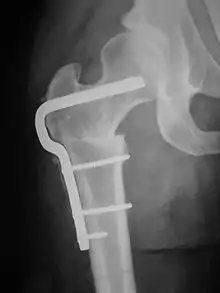

A subtrochanteric blade plate or an intramedullary rod can be used to stabilize the osteotomy site in a femoral derotation osteotomy until compete bone healing is achieved; an approach employing an intramedullary rod is much less invasive than one using a subtrochanteric blade plate.